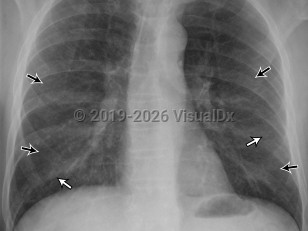

Extrinsic allergic alveolitis

Extrinsic allergic alveolitis manifests acutely with sudden-onset chest pain, cough, dyspnea, and fever following exposure to antigens. Headache, bibasilar crackles, inspiratory crackles, and malaise develop within 4-6 hours after exposure and may clear within 24 hours after removing the offending substance.

The subacute form manifests gradually and less severely and may recur infrequently. A chronic form, present in half of patients, is characterized by an insidious onset of cough, fatigue, progressive dyspnea, and weight loss. Tachypnea, respiratory distress, and clubbing portend a poor prognosis.